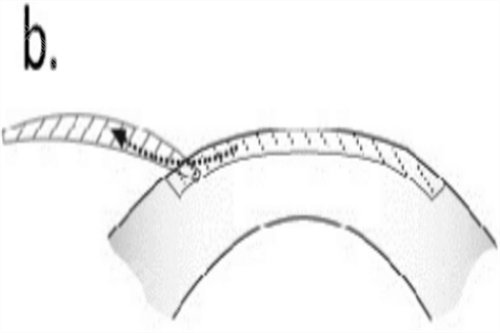

全飞秒激光手术:15800元/双眼